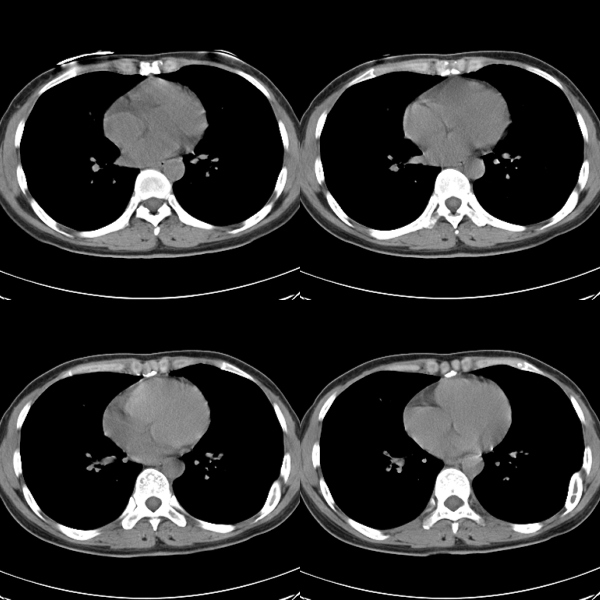

标题: CT19623:F40y,肋骨改变。

40岁女性,双侧胸部疼痛,以左侧为明显1+年。余无明显异常。

左侧肋骨单发膨胀性病变,皮质连续,病史较长,首先考虑良性病变:骨纤可能性大。